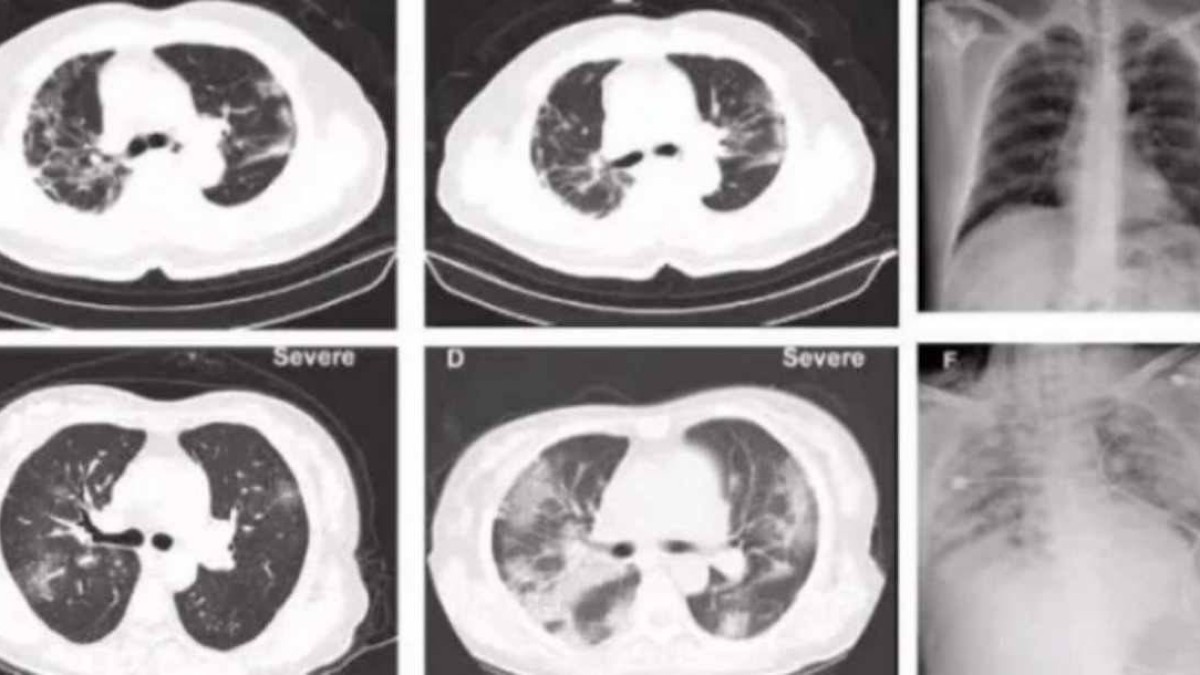

Ауруханаға жеткізілгенде науқастың қызу, жөтел және басқа да вирус белгілері байқалмаған. Ауруханаға түскеннен кейінгі 10- күні науқастың тамағында қышу пайда болып қызуы көтерілген. Компьютерлік томографиядан оны4 екі өкпеcінде инфекция бар екені көрінді.

20-күні өкпеге жасалған томографияда инфекция одан әрі таралып жатқаны көрінген. 28-ші күні науқас көз жұмып, оған «коронавирустың жаңа түрінен туындаған пневмония, тыныс алу жеткіліксіздігі» деген диагноз қойылған.

«Біз «дұшпанның» қай жерде екенін, оның «қаруы» не екенін, күшін білмейміз. Патологиялық анатомия мен кейінгі зерттеулердің арқасында вирустың адам ағзасына таралуын микроскоптың көмегімен байқауға болады. Қандай мүшелер, ұлпалар мен жасушалар ең көп зардап шеккенін, «жаудың» әлсіздігі не екенін түсінуге болады. Компьютерлік томографиясы науқастың өкпесінде өзгеріс белгілерінің пайда болуын көрсетті », - дейді дәрігер Лю Лян.